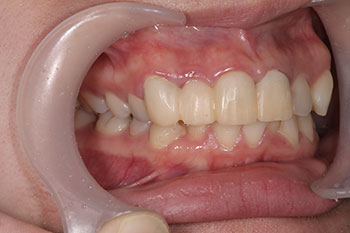

口元が少し出ているのと、前歯の咬み合わせが気になりご相談に来られた患者様です。小さい頃から欠かさずに定期検診に来られていた患者様で、歯垢も少なくむし歯もないのですぐに矯正治療を始める予定でしたが、転んでしまい歯が少し動揺していましたので、落ち着いてからの進行となりました。

今回はインビザラインGoによる部分矯正とマルチブラケット装置による全体矯正、インビザラインによるマウスピース全体矯正を提案させていただきました。患者様のご要望とカウンセリングにてお話させていただいたそれぞれのメリットやデメリットから考えていただき、今回はインビザラインGoでの治療を選択されました。